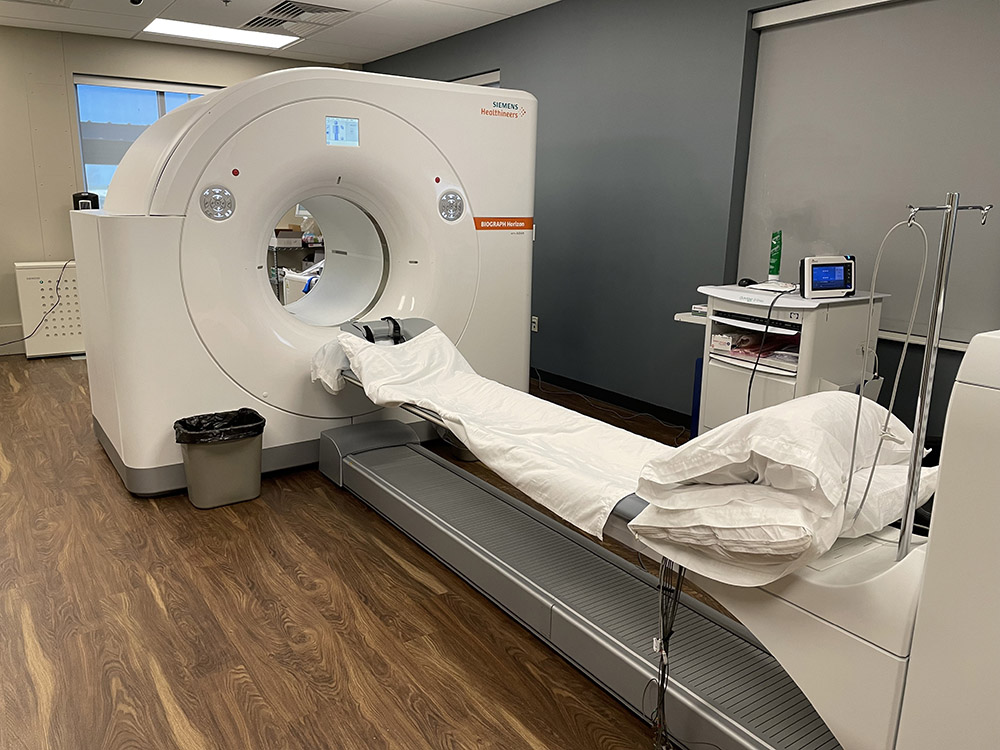

Enhance your business with our stunning commercial Cardiac Pet/ct collection of numerous professional images. optimized for commercial use with truck, vehicle, and automobile. ideal for corporate communications and branding. Discover high-resolution Cardiac Pet/ct images optimized for various applications. Suitable for various applications including web design, social media, personal projects, and digital content creation All Cardiac Pet/ct images are available in high resolution with professional-grade quality, optimized for both digital and print applications, and include comprehensive metadata for easy organization and usage. Discover the perfect Cardiac Pet/ct images to enhance your visual communication needs. Our Cardiac Pet/ct database continuously expands with fresh, relevant content from skilled photographers. Reliable customer support ensures smooth experience throughout the Cardiac Pet/ct selection process. Professional licensing options accommodate both commercial and educational usage requirements. Multiple resolution options ensure optimal performance across different platforms and applications. Regular updates keep the Cardiac Pet/ct collection current with contemporary trends and styles. Each image in our Cardiac Pet/ct gallery undergoes rigorous quality assessment before inclusion. Time-saving browsing features help users locate ideal Cardiac Pet/ct images quickly. The Cardiac Pet/ct archive serves professionals, educators, and creatives across diverse industries. Comprehensive tagging systems facilitate quick discovery of relevant Cardiac Pet/ct content.